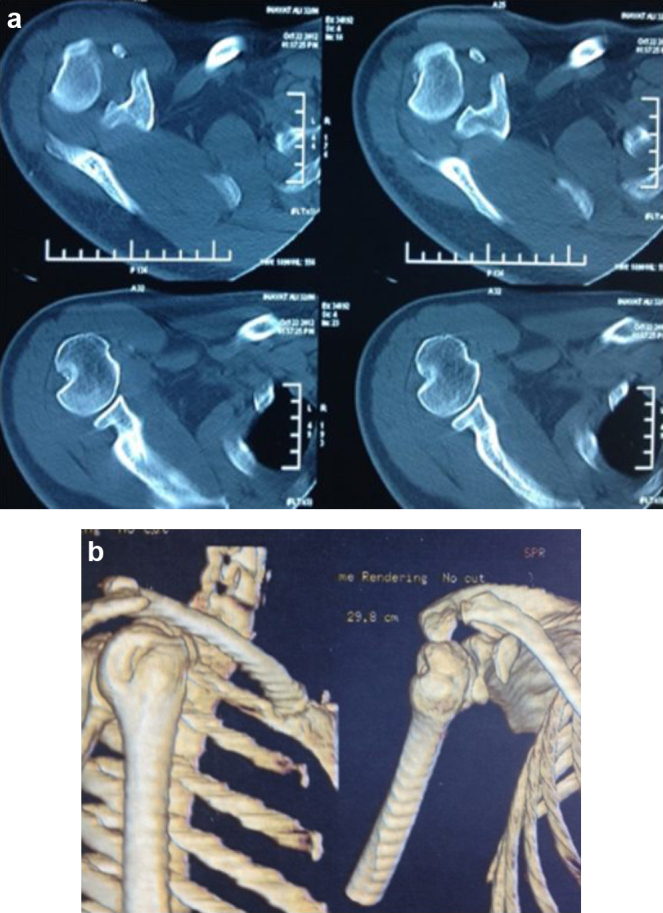

MR imaging revealed the Bankart's lesion and wedge shaped depression along the postero-lateral aspect of the humerus suggestive of Hill-Sach's lesion (Fig. 2a and b). Pre-operative CT scan showed Hill-Sach's lesion associated with coracoid process fracture (Fig. 3). Glenoid bony deficiency as measured on 3DCT scan was <25%, not considered as significant.

Fig. 3.

CT scan (a) showing Hill-Sach's lesion and (b) coracoid process fracture.

The association of an anterior dislocation of the shoulder and a fracture of the coracoid process is very unusual. It is often unrecognized because of poor knowledge of this lesion and also the likelihood of them being missed due to poor quality of the radiographs performed in the emergency room.6 In our case, although radiographs did not reveal the fracture, pre-operative CT scan clearly demonstrated coracoid fracture along with significant Hill-Sach's lesion. The diagnosis of associated coracoid fracture requires good clinico-radiological examination with a lateral axillary view centered at coracoid performed after reducing the shoulder, which shows the fracture more clearly. Antero-posterior Cephalic Tilt View, Stryker Notch views have also been described to identify this innocuous fracture.22 However the best investigation remains CT scan with 3D reconstruction which can show associated injuries as well.23